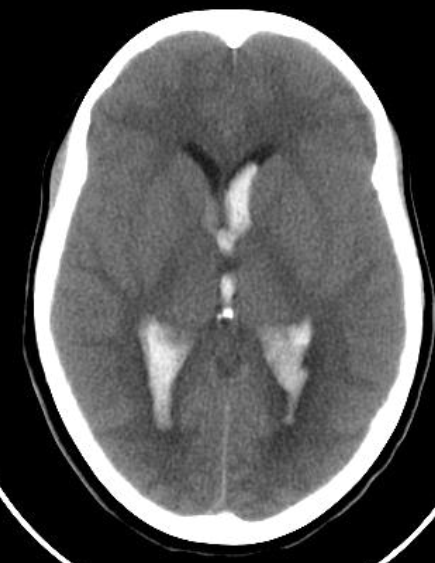

CT brain - Hydrocephalus

Axial T2-weighted MRI - Cerebral atrophy

showing prominence of the ventricles and generalized widening of

the cerebral sulci in keeping with age-related atrophy.

Intra ventricular hemorrhage

- Anterior/Posterior Horns hemorrhages

- 3rd ventricles